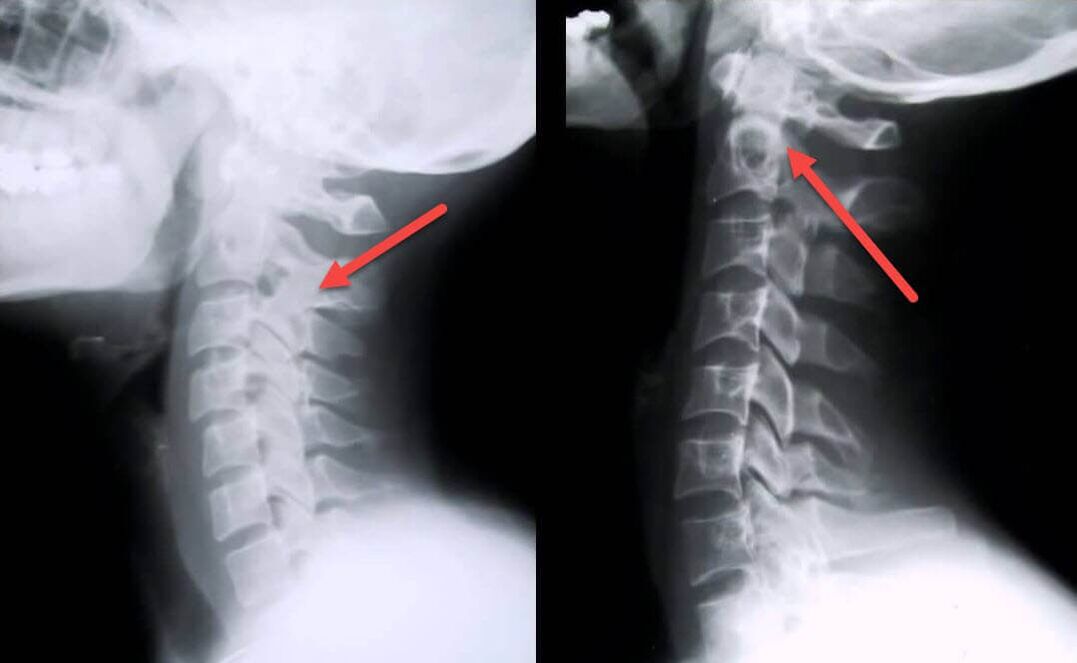

The most informative diagnostic procedure is radiography.1st degree pathologies correspond to the 1st or 2nd radiological stage.The resulting images visualize typical signs of the disease.

| Radiographic stages of 1st degree cervical osteochondrosis | Characteristic signs |

|---|---|

| Stage 1 | Small changes in the curvature of the spine in the cervical region, affecting one or more segments |

| Stage 2 | Slight thickening of the intervertebral discs, deformation of the uncinate processes, straightening of the lordosis, small growths of the bony structures |

Sometimes MRI is necessary to clarify the diagnosis.With its help, it is possible to detect an aseptic, sluggish inflammatory process and destructive-degenerative changes in the intervertebral discs.